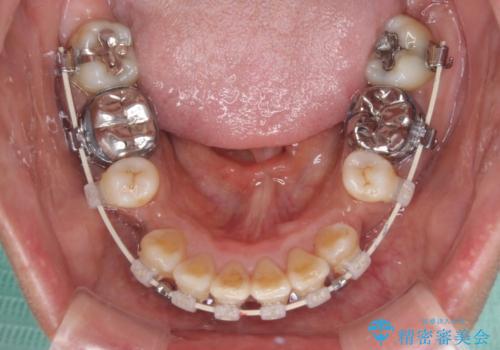

- 審美装置

- 2年4ヶ月

- 10-30回

- 八重歯やクロスバイトを気にして来院された患者様です。

口元の突出感はありませんでしたが、デコボコが強く、非抜歯矯正とすると出っ歯仕上がりとなる可能性があったため、上下左右の第一小臼歯4本を抜歯し、ワイヤー装置にて矯正治療を行うこととしました。